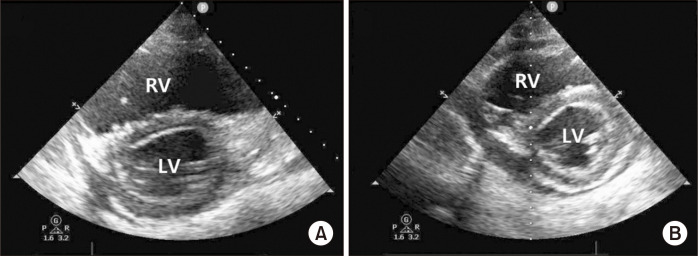

静脉体外膜氧合(VV ECMO)常用于严重呼吸衰竭的病例,尤其是考虑进行肺移植的患者。然而,由于许多肺部疾病最终会导致右心衰竭,当患者已经接受静脉体外膜肺氧合(VV ECMO)支持时,继发性右心衰竭的治疗可能会面临挑战。在这种情况下,可以使用氧合右心室辅助装置(OxyRVAD)。OxyRVAD 的设计旨在维持前向血流,防止右心室扩张。此外,肺动脉插管可经皮插入。我们报告了一例经皮 OxyRVAD 成功用于治疗呼吸衰竭患者右心衰竭的病例,患者当时正在接受 VV ECMO。

Venovenous extracorporeal membrane oxygenation (VV ECMO) is often used in cases of severe respiratory failure, especially in patients considered for lung transplantation. However, because many lung diseases can ultimately result in right heart failure, the treatment of secondary right heart failure can present a challenge when the patient is already under VV ECMO support. In such cases, an oxygenated-right ventricular assist device (OxyRVAD) can be used. OxyRVAD is designed to maintain anterograde blood flow and prevent right ventricular distension. Moreover, the pulmonary arterial cannula can be inserted percutaneously. We report a case in which percutaneous OxyRVAD was successfully implemented to manage right heart failure in a patient with respiratory failure who was on VV ECMO.